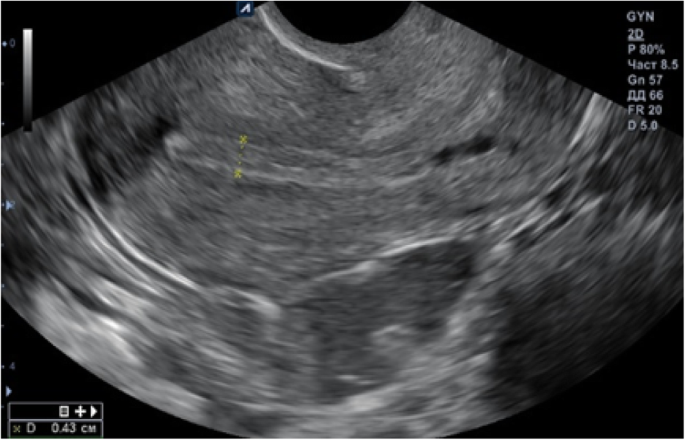

IVF was proposed. In August 2018, ovulation was stimulated with gonadotropins according to the short protocol, after which 12 embryos were obtained and cryopreserved on day 5, because according to ultrasound, the thickness of the endometrium was 0.4 cm. During subsequent consultations, the patient complained that her menstruation was scarce and lasted 2–3 days. In October 2018, the patient began medication preparation for frozen embryo transfer according to the long protocol. On the 19th day of her menstrual cycle, gonadotropin-releasing hormone (GnRH) agonist 3.75 mg was administered intramuscularly. Sixteen days after the injection, the patient received estradiol valerate 2.0 mg, two tablets daily; folate 800μg, one tablet daily; and from the 16th day of the menstrual cycle, progesterone 200 mg, one tablet three times daily. According to ultrasound monitoring of the patient’s endometrium during the cycle, the thickness of the endometrium did not exceed 0.4 cm (Fig. 1). Therefore, the embryo transfer was canceled.